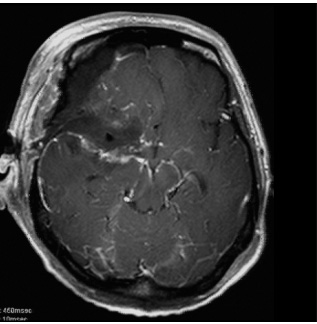

症例3は42歳女性。意識消失にて発症。CT、MRIにて内頸動脈、中大脳動脈を巻き込む大型の前床突起部起源の髄膜腫を認める。

中大脳動脈の血流が低く、血管損傷を来す可能性もあるので、浅側頭動脈-中大脳動脈バイパスをおいた後に腫瘍内より血管を掘り起こすように摘出を行った。

細い脳深部に至る血管も保護して摘出した。術後四肢麻痺等なく回復。

術前画像:内頸動脈などの血管を巻き込み狭窄する(反対側と比較)腫瘍をみとめ周囲に脳の腫れを認める。

術後画像:腫瘍はほぼ摘出され、脳梗塞等の合併症は認めない。